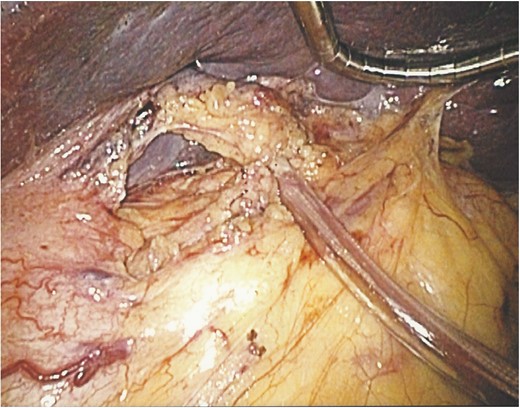

An operative image showing the splenic cyst after de-capsulation with a bloodless bed and minimal bleeding from edges of the cyst.

Computed tomography showing medial displacement of the stomach and the left kidney by the cyst.

An operative image showing the splenic hilum slung with the vascular tape and clamped with a segment of a nasogastric tube.